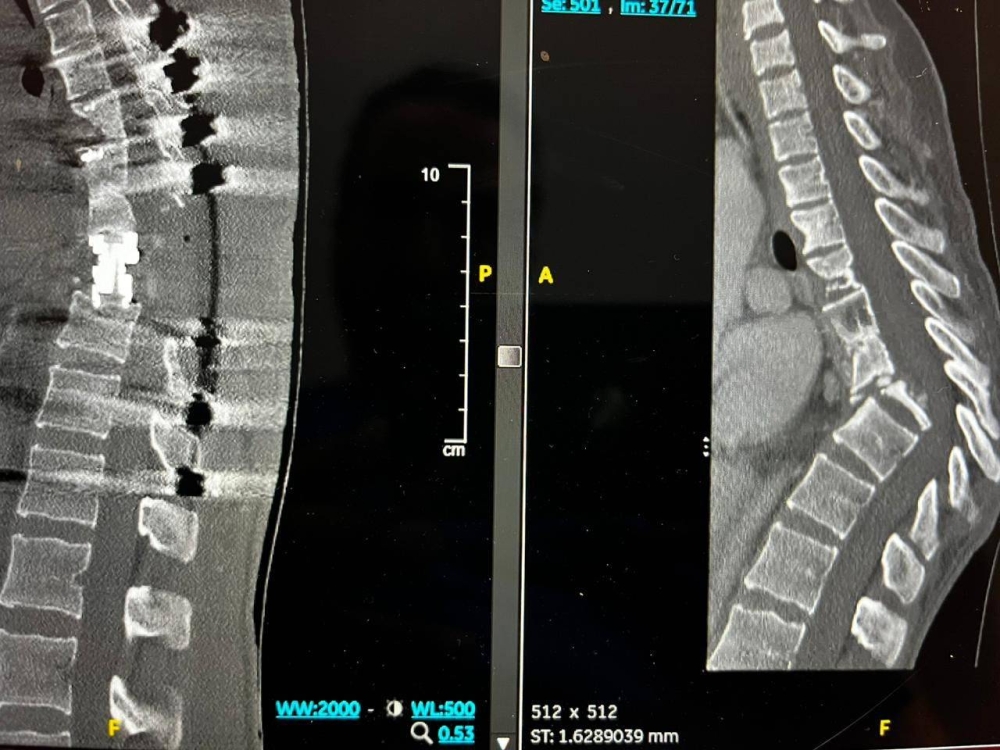

وكانت المريضة التي تبلغ من العمر 27 عامًا، تعاني من مرض الذئبة الحمراء وهشاشة العظام ومصابة بداء الدرن في العمود الفقري، وفور وصولها إلى مدينة الملك فهد الطبية، أجريت لها الفحوصات الطبية والتي أظهرت وجود سوائل في العمود الفقري، بسبب تدهور حالتها الصحية، وتهتك في العمود الفقري وتشوه معقد يتكون من تحدب وتزحزح للفقرات الصدرية وضغط على الحبل الشوكي في مكان التشوه.

وعلى الوقت ذاته، خضعت المريضة في بداية مرحلة العلاج إلى سحب السوائل من العمود الفقري وعلاج الدرن، وهشاشة العظام الأمر الذي سهل من مراحل الخطة العلاجية، الأمر الذي جعل الفريق الطبي يؤكد على قراره في إجراء العملية والتي استمرت 12 ساعة متواصلة تمكنوا خلالها من فتح الظهر وزراعة وسائل التثبيت، حيث تلاها بعدة أيام قص العظام الخلفية والأمامية للعمود الفقري ووضع دعامة لتصحيح العمود الفقري للشكل الطبيعي مع المحافظة على سلامة الحبل الشوكي.